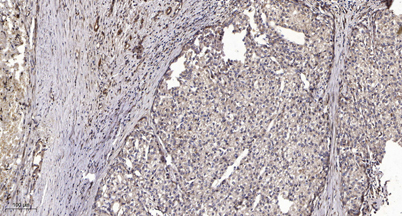

Immunohistochemical analysis of paraffin-embedded human liver cancer. 1, Antibody was diluted at 1:200(4 overnight). 2, Tris-EDTA,pH9.0 was used for antigen retrieval. 3,Secondary antibody was diluted at 1:200(room temperature, 45min).